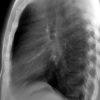

Lao hạch

» Thông tin: Nam giới – 27 tuổi.

» Lâm sàng: Đau ngực / Nuốt khó.